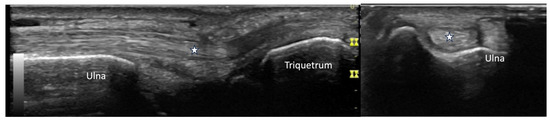

4.2. Evaluation of the Wrist

4.2.3. Ulnar Aspect